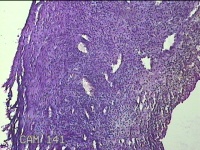

右侧卵巢囊肿

性别

女

年龄

36岁

临床诊断

一般病史

发现双侧附件囊肿1年。

标本名称

大体所见

灰白暗红色囊壁样组织2.5x2x0.3cm一块,表面光滑,部分已切开,囊内容物已流失,囊壁厚0.2cm。

考虑:子宫内膜异位囊肿。